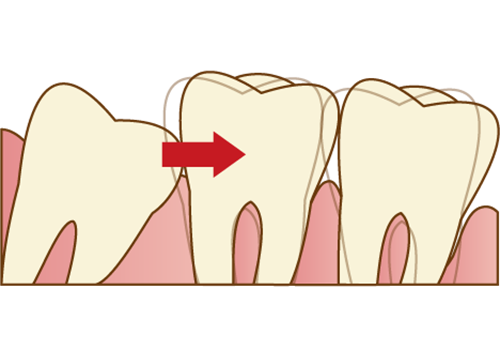

親知らずが斜めや横向きに生えている場合

親知らずがまっすぐ生えておらず、斜めや横向きになっている場合、汚れが溜まりやすく虫歯や歯周病のリスクが高い状態になっていると言えます。

身体が健康で免疫力が高く、しっかりと口腔ケアができているときは症状が抑えられますが、体の免疫力が落ちたり、妊娠出産などで歯周病リスクが高まる時期にトラブルを起こしてしまうケースが多々あります。

また、親知らずが隣の歯を押すことで、歯並びが悪くなったり歯が弱くなったりしてしまう可能性もありますので、将来的にトラブルが予想される親知らずの場合は早めに抜いておくことをおススメします。